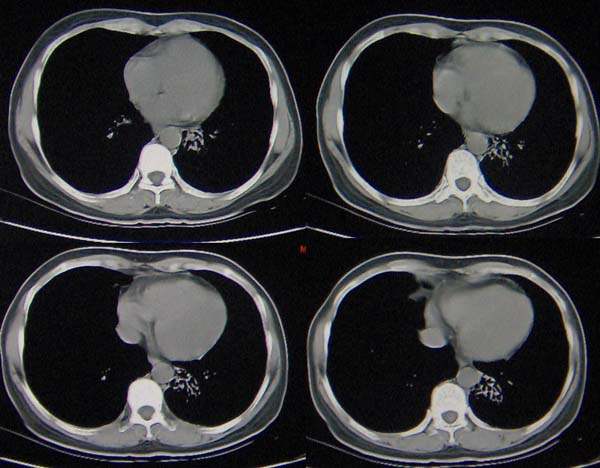

肺隔离症伴支扩(肺外型)或肺发育不良。

1,左肺下叶支气管扩张?

2,肺隔离症?

现有的征象提示左肺支扩并双肺炎症。至于隔离肺可以考虑但缺少证据。

双肺炎症;左下支扩并感染,肺隔离症待排

两肺炎症;左下支扩;左下肺副叶!

左肺舌叶及右肺下叶背段斑片状低密度影,左肺下叶内基底段网格状阴影,周围肺野透亮度增高,结合临床咳嗽、发热,38度,无咯血及反复感染病史,考虑双肺炎症,左下肺发育不良。建议抗炎治疗后复查或增强与左下肺隔离症鉴别。